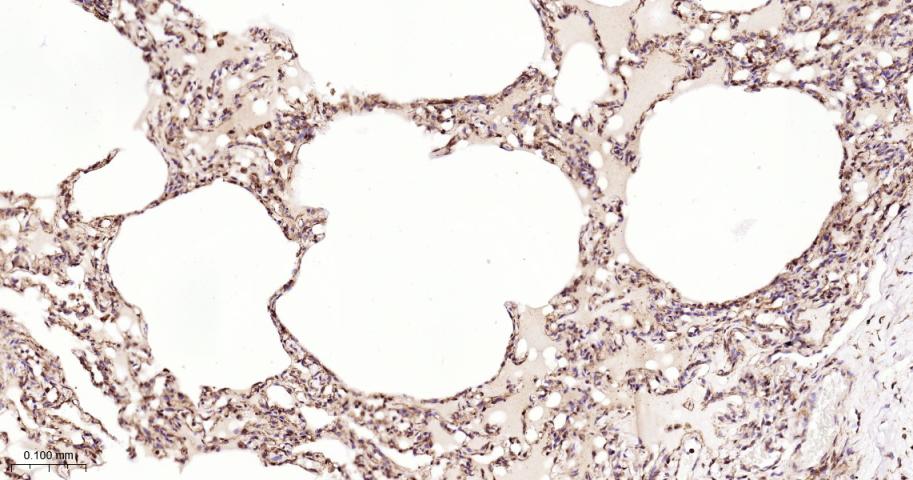

Paraformaldehyde-fixed, paraffin embedded Human Lung; Antigen retrieval by boiling in sodium citrate buffer (pH6.0) for 15 min; The section was incubated with USP10 Monoclonal Antibody, Unconjugated (bsm-61654R) at 1:200 overnight at 4°C, followed by conjugation to the bs-0295G-HRP and DAB (C-0010) staining.